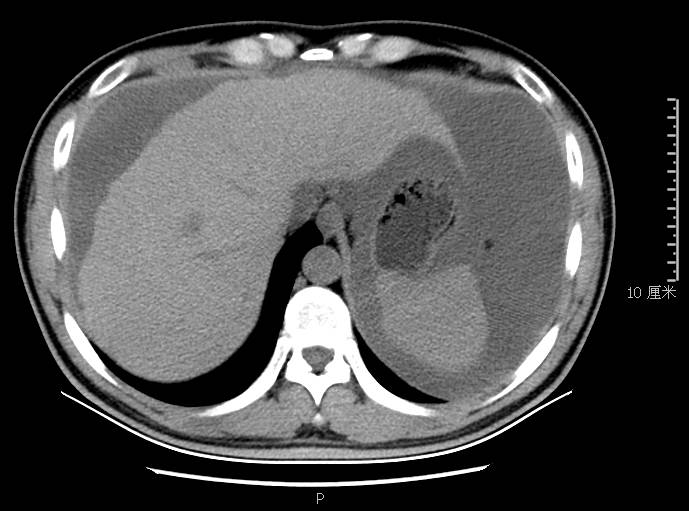

全腹CT:(1)结合病史考虑腹膜炎(见图2A),大量腹水;(2)右骼窝区管状样结构,考虑阑尾扩张(见图2B);(3)肝脏多发小囊肿(见图2C);(4)肝内胆管轻度扩张,建议隔期复查。

本例确诊后对B超及CT再次回顾发现:腹腔、盆腔可见不均质中强回声包块,部分呈囊实状,腹膜增厚,大网膜成饼状(如图2A)和肝周可见不均质中强回声弧形压迹、脾周可见不均质中强回声包饶,肝脏成扇贝样改变(如图2C),但在诊断报告中未提及。有学者发现mantle和scalloping(如图2A,2C)在PMP中具有代表性,且mantle较scalloping更为常见,若mantel征同时伴有大小不一的囊性改变,则更具诊断价值。

图2c肝脏成扇贝样改变(肝脏由于受肿瘤实质性或囊性组织压迫而其实质却未受侵犯,于是在一处或多处呈下凹状或扇形皱褶状(scalloping)